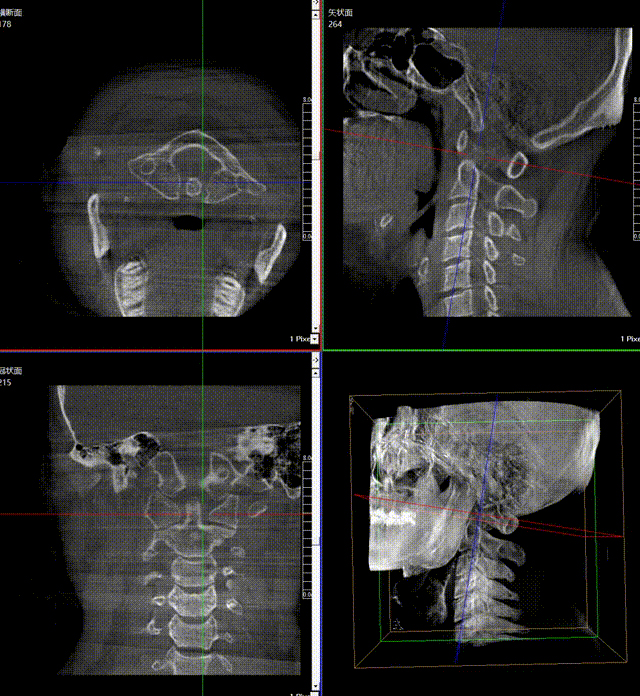

通常上頸椎的手術是非常復雜的,因為醫(yī)生要把釘子打在上頸椎這樣一個很狹小的通道里面,周圍都是重要的神經(jīng)血管,一旦損傷到頸椎,就有可能造成病人的死亡。隨著醫(yī)學影像技術的不斷發(fā)展,在三維影像的引導下,整個打進去的通路能夠完全的展現(xiàn)在我們的眼睛里,讓這種復雜的手術變得簡單了,更多的醫(yī)生就可以去開展這樣的手術了,也會有越來越多的病人從中獲益。